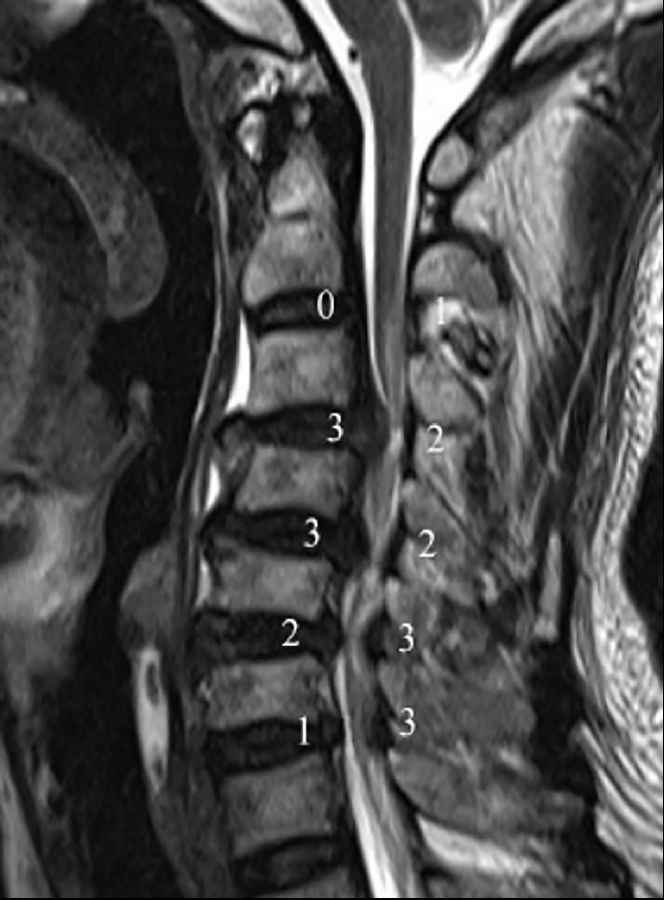

3.1颈椎MRI矢状位脊髓压迫比值

依据Fehlings等报道的方法测量颈椎MRI矢状位脊髓压迫比值(compression ratio of the spinal cord,CRS)。分别测得颈椎MRI矢状位,压迫程度最重节段脊髓直径(dc),上方椎体水平非压迫节段脊髓直径(ds)以及下方椎体水平非压迫节段脊髓直径(di)(图1)。其中选择MRI正中矢状位或旁矢状位测量,依据颈椎间盘压迫位置,分为中央型与旁中央型。CRS具体测量公式如下:

3.2 颈椎间盘突出程度

颈椎间盘突出程度依据颈椎MRI矢状位椎管压迫比值(compression ratio of the cervical spinal canal,CRCS)。椎管压迫比值CRCS与脊髓压迫比值CRS测量方法类似,只是前者测量的是椎管整体压迫程度,后者关注的是脊髓本身压迫程度。分别测得颈椎MRI矢状位压迫程度最重节段椎管直径(Dc),上方椎体水平非压迫节段椎管直径(Ds)以及下方椎体水平非压迫节段椎管直径(Di)(图1)。CRCS具体测量公式如下:

之后依据CRCS比值,将患者分为间盘严重突出组(CRCS>30%)及间盘非严重突出组(CRCS≤30%)。

图1.颈椎MRI矢状位脊髓压迫比值和颈椎间盘突出程度的测量方法。颈椎MRI矢状位,压迫程度最重节段脊髓直径(dc),上位椎体水平非压迫节段脊髓直径(ds)以及下位椎体水平非压迫节段脊髓直径(di);压迫程度最重节段椎管直径(Dc),上位椎体水平非压迫节段椎管直径(Ds)以及下位椎体水平非压迫节段椎管直径(Di)

颈椎节段后凸角度测量使用Harrison椎体后切线法,此测量方法相较Cobb角法对颈椎后凸的评估更可靠。本研究中,我们尝试探索退变性颈椎后凸对神经功能的影响,Harrison椎体后切线法更直接评估椎体后缘成角而非椎体上下终板交角对脊髓的影响,可能会提高测量结果与脊髓神经功能损害程度的相关性(图1)。分别测量了在颈椎MRI矢状位像上、颈椎侧位X线、过屈位X线及过伸位X线上的颈椎节段角度。本研究中颈椎前凸角度定为负值,颈椎后凸角度定为正值,以°为标准界定颈椎后凸。